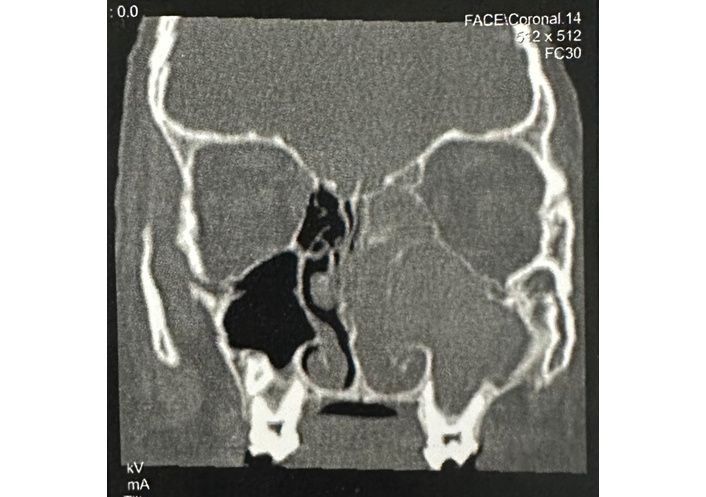

Coronal CT showed opacification of the frontal sinuses, left maxillary sinus, and increased density of left ethmoid cells, as well as evidence of bone remodeling. There was also a deviation of the nasal septum to the right and extensive involvement of the frontal sinuses, left maxillary sinus, and ethmoid cells, extending into the nasal fossa, with an expansive appearance and dense content causing ipsilateral anterior bulging at the medial anterior ethmo-orbital margin, displacing the retro-medial muscle and adjacent orbital fat, impinging upon the eyeball.

CT showed opacification of the frontal sinuses, left maxillary sinus, and increased density of left ethmoid cells, as well as evidence of bone remodeling with bulging of the medial wall of the left maxillary sinus, bulging of the left orbital lamina, thinning of the left ethmoidal trabeculae, as well as mucosal thickening in the sphenoidal sinus. There was also a deviation of the nasal septum to the right and extensive involvement of the frontal sinuses, left maxillary sinus, and ethmoid cells, extending into the nasal fossa, with an expansive appearance and dense content, causing ipsilateral anterior bulging at the medial anterior ethmo-orbital margin, displacing the retro-medial muscle and adjacent orbital fat, impinging upon the eyeball. Consideration should be given to benign tumors, fungal sinusitis, and esthesioneuroblastoma.

A 12-year-old immunocompetent male patient was admitted to our department (Figure 1) with a 3-month history of left-sided nasal obstruction for which he had received systemic therapy with antihistamine and steroids without improvement. He had a personal and family history of allergic rhinitis and initiated allergen-specific immunotherapy at 5 years of age. However, the treatment was discontinued after 6 months. No symptoms of asthma were reported, and spirometry demonstrated normal values. He also complained of left periorbital swelling with eye ipsilateral proptosis. Computed tomography (CT) showed opacification of the frontal sinuses, left maxillary sinus, and increased density of left ethmoid cells, as well as evidence of bone remodeling with bulging of the medial wall of the left maxillary sinus, bulging of the left orbital lamina, thinning of the left ethmoidal trabeculae, and mucosal thickening in the sphenoidal sinus. There was also a deviation of the nasal septum to the right and extensive involvement of the frontal sinuses, left maxillary sinus, and ethmoid cells, extending into the nasal fossa, with an expansive appearance and dense content, causing ipsilateral anterior bulging at the medial anterior ethmo-orbital margin, displacing the retro-medial muscle and adjacent orbital fat, impinging upon the eyeball. Consideration should be given to benign tumors, fungal sinusitis, and esthesioneuroblastoma. There was a slight external deviation of the left eyeball (Figure 2). He was started on prednisolone 20 mg daily for two weeks in the preoperative period, and the dose was subsequently tapered to 20 mg on alternate days until the postoperative follow-up visits at 30 days. Patient underwent functional endoscopic sinus surgery (FESS) and polypectomy. Histopathological analysis showed eosinophilic amorphous material with associated inflammatory infiltrates and degenerated epithelial cells, adjacent to bone fragments (Figure 3A and B). Grocott’s methenamine silver (GMS) revealed fungal elements (Figure 3C). The direct microscopic examination showed the fungus (Figure 3D). A fungal culture grew Curvularia species (Figure 3E and F). In addition, the patient’s serum IgE was markedly elevated at 1,963 IU/mL (normal < 200 IU/mL), blood eosinophil counts were 51 cells/L, fungal-specific IgE and mite-specific IgE were positive. During the postoperative follow-up visit, the prednisolone dose was increased to 30 mg daily, followed by a stepwise tapering of 5 mg every two weeks until discontinuation. In addition, the patient was prescribed intranasal mometasone furoate and nasal rinsing with saline as maintenance therapy. No adverse events were observed in the patient. After surgery, he was symptom-free, and the frontal/maxillary sinus mucosa maintained its normalized state. The patient remained free of recurrence over a two-year follow-up period.